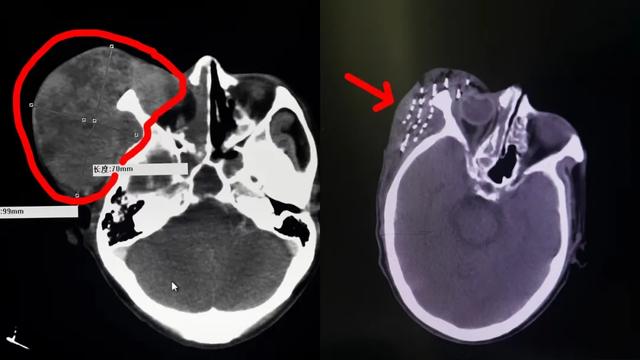

“饿死”肿瘤: 通过“栓塞术”,堵死为肿瘤输送养分的血管,断其粮草,让它自然萎缩。“毒死”肿瘤: 通过“动脉灌注”,将化疗药像“精确制导导弹”一样,只投送到肿瘤内部,实现高效杀灭,同时避免“毒害”全身。“烧死/冻死”肿瘤: 对引发疼痛、梗阻等症状的关键病灶,用微波/射频“加热”,或用氦氩刀“深冻”,进行定点清除,快速缓解痛苦。“内部瓦解”肿瘤(持久围剿): 这便是放射性粒子植入术。我们可以通过一根细针,将像米粒大小的放射性源直接植入肿瘤内部。让这些“深水炸弹”24小时、持续不断地从内部照射和摧毁肿瘤细胞,而对周围的正常组织损伤极小。这是一种“润物细无声”的持久战,尤其适合一些局部的、顽固的病灶。这一切的目的,不是为了追求一个虚无的“完全清除”,而是为了实现一个更现实、也更宝贵的目标:“带瘤高质量生存”——让你在有效控制病情的同时,还能吃得下、睡得着、有力气散步、有精神与家人说笑。 保住你作为人的基本生活质量和尊严。